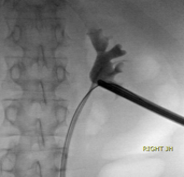

After placement over the wire, the sheath obturator is removed, leaving the safety wire in place. The sheath endcap and suction are placed. The 12-Fr mini nephroscope is inserted to obtain endoscopic access and identify the stone in the renal calyx.

Once endoscopic access has been obtained, TFL lithotripsy is carried out. The energy settings should be adjusted according to the stone’s composition; however, I recommend 20-30 watts in the renal pelvis and intrarenal system; my preferred setting for large stones is 1.5 J with 20 Hz in fragmentation mode in short pulse. For Mini-PCNL I use 365 mc fiber, this allows me to use the same fiber through a flexible ureteroscope in an antegrade manner if needed

Manipulation of the sheath to place the tip near the stone fragments allows for optimal suction. Stone dust and stone fragments are actively suctioned away from the field of view. Then, all calyces and the UPJ are inspected to see that all fragments have been suctioned. Finally, an antegrade nephrostogram is performed prior to stent placement. The stent is placed under fluoroscopic guidance ensuring the distal curl is in the bladder, and the proximal curl is developed endoscopically and confirmed on fluoroscopy.